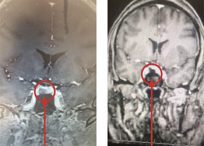

Dr. Brisman is proficient in the use of minimally-invasive, neurosurgical procedures including:

- Microvascular Decompression

- Transsphenoidal Surgery

- Trigeminal Neuralgia

- Hemifacial Spasm

- Glossopharyngeal Neuralgia